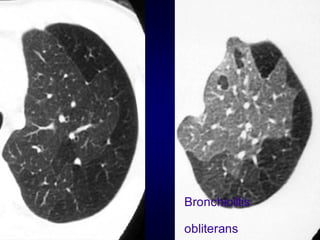

Bronchiolitis obliterans (constrictive bronchiolitis)

idiopathic, connective tissue diseases, drug reaction,

after transplantation, after infection

Hypersensitivity pneumonitis

granulomatous inflammation of bronchiolar wall

Sarcoidosis

Asthma / Bronchiectasis / Airway diseases

Airway Disease

what you see……

In inspiration

sharply demarcated areas of seemingly increased

density (normal) and decreased density

demarcation by interlobular septa

In expiration

„black‟ areas remain in volume and density

„white‟ areas decrease in volume and increase in

density

INCREASE IN CONTRAST

DIFFERENCES

AIRTRAPPING

Bronchiolitis

obliterans

Early Sarcoidosis

Chronic

EAA